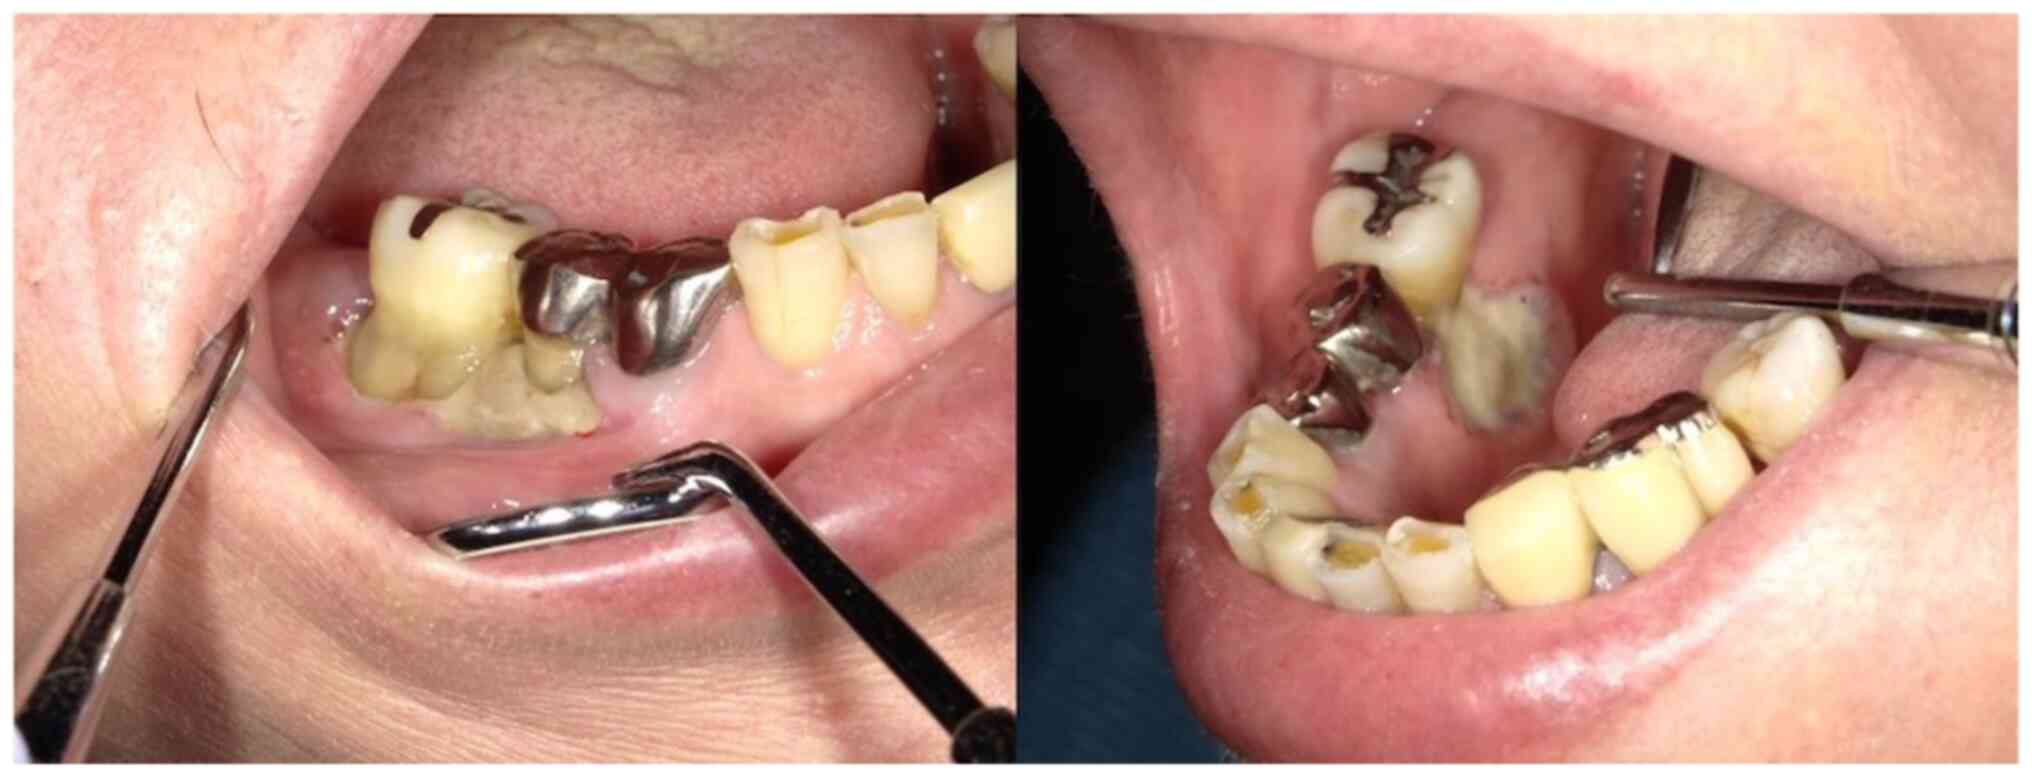

Methotrexate‑related other iatrogenic immunodeficiency‑associated lymphoproliferative disorder (MTX‑OIIA‑LPD) is prone to extranodal involvement but rarely involves the central nervous system (CNS). The present study reports a case of MTX‑OIIA‑LPD of the CNS discovered during medication‑related osteonecrosis of the jaw (MRONJ) treatment in a 76‑year‑old woman with rheumatoid arthritis (RA). The chief complaint of the patient was bone exposure and pain in the right mandibular molar. The patient had been receiving MTX for RA and alendronate sodium hydrate for osteoporosis, followed by denosumab. Treatment was initiated based on a diagnosis of MRONJ. However, the patient experienced lightheadedness and floating dizziness afterwards. Examinations revealed scattered neoplastic lesions in the brain. The histopathological diagnosis was diffuse large B‑cell lymphoma. A systemic search also revealed adrenal involvement. Since the patient was taking MTX, a diagnosis of MTX‑OIIA‑LPD was made and MTX was discontinued. Chemotherapeutic agents were administered since the central lesions became symptomatic. The MTX‑OIIA‑LPD lesions in the brain and adrenal glands completely resolved 8 months after onset. The physical condition of the patient improved, and the bone‑exposed areas became epithelialized. Reports on MTX‑LPD in the oral and maxillofacial region are few, which may delay its diagnosis. Therefore, biopsy of oral lesions in patients with MRONJ who are taking MTX and collaboration with related diagnostic departments, such as rheumatology and hematology, must be done to initiate the diagnosis and treatment of extraoral MTX‑LPD.